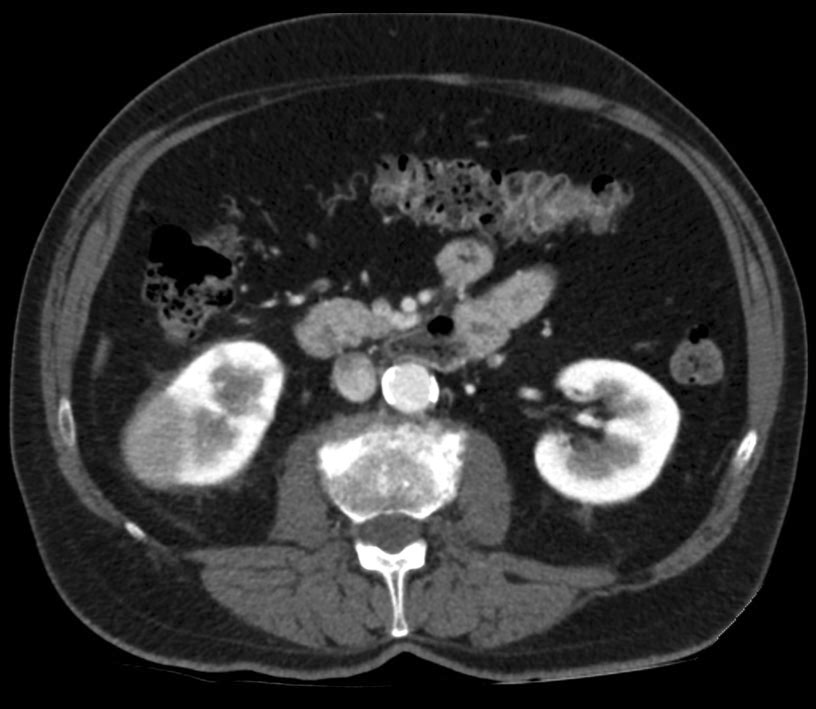

Eco y TC abdominal de control.